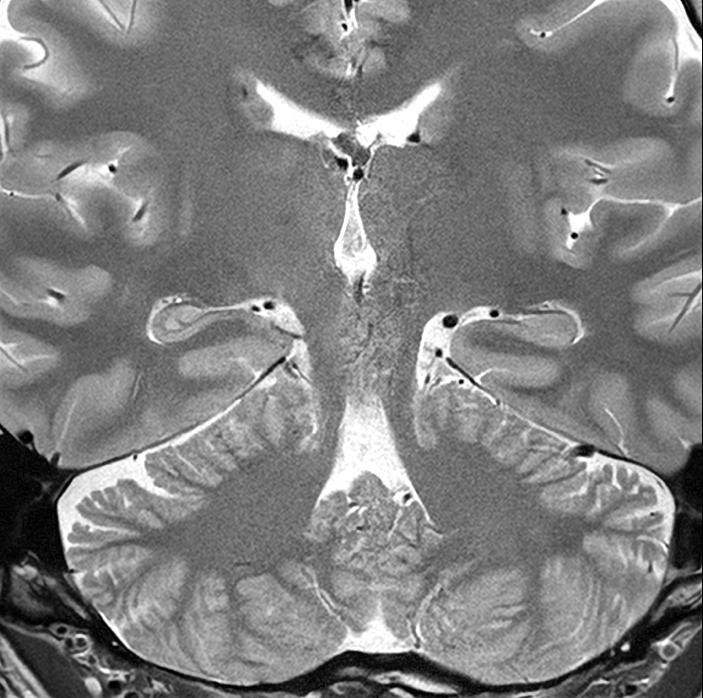

Figure 2, Axial MRIs of the brain. Left: T1-weighted image (short TE and TR). Right: T2-weighted image (long TE and TR). Figure 3, Olea Nova + software. Top row: MP2RAGE images from which the T1-map is calculated and FSE mEcho images used to calculate the T2-map. Bottom row: Two synthetic images with different imaging parameters.

Canon Medical MR systems require two sequences to be able to calculate T1 and T2 relaxation times. To measure the T2-relaxation time, we use a 2D FSE mEcho (2D Fast Spin Echo Multi-Echo) sequence. This sequence acquires the signal multiple times after an excitation pulse (illustrated by dots in the T2-relaxation graph in Figure 1). The longer the time between the excitation and the signal acquisition (TE), the smaller the transverse magnetization becomes. This is an exponential process and the Olea software fits the data points to obtain the T2-relaxation time (Figure 3 – top right).

For the computation of the T1 relaxation time, we use a MP2RAGE sequence (Magnetization Prepared 2 RApid Gradient Echo). This sequence starts with inverting the longitudinal magnetization of all tissues and samples the regrowth of the magnetization at two different time points after this inversion. In the Olea software, the signal intensity at these two time points is fitted and the T1 relaxation time is determined at each voxel (Figure 3 – top middle). Before the fitting process of both the T1 and T2 relaxation times, motion correction is applied.

Now that the T1 and T2 relaxation time is known at every position in the image, the software can synthesize new contrasts using signal equations that describe the signal intensity based on the T1, T2, TE, TR and TIs (inversion times). To create a T1-weighted

image, a short TE and TR can be selected. The software then calculates the contrast obtained with these settings, presenting the result immediately. This new synthetic image can be saved and exported. To change the contrast again, the parameters can be altered (Figure 4) and a new image is created, without the patient needing to be present.